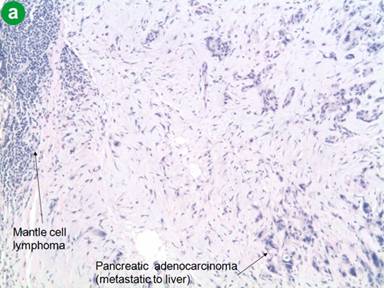

On follow-up in May 2012, the patient reported feeling generally well, except for a new onset of abdominal discomfort, occurring 30 minutes after eating, lasting for 30-60 minutes and associated with diarrhea. He did not complain of other new symptoms. A PET/CT after eight cycles of chemotherapy indicated a near-complete disappearance of the disease at the level of spleen and lymph nodes, but a new mass at the tail of the pancreas measuring 2.0x2.5 cm (Figure 2). Several small (5 mm) hypodense lesions were noted in the liver. These findings were not present on the PET/CT done after the sixth cycle of chemotherapy. To evaluate the focal area of persistent uptake in the pancreatic tail, a CT scan was done in June 2012. It confirmed the mass in the tail of the pancreas, highly suspicious for malignancy (Figure 3). His anemia and thrombocytopenia remained stable. The white blood cell count was within normal range, but showed persistently decreased absolute lymphocyte count. Serum IgG and IgM immunoglobulin levels were decreased to 642 mg/dL (reference range: 782-1,195 mg/dL) and 31 mg/dL (reference range: 53-334 mg/dL), respectively. Serum IgA was normal. CA 19-9 level was elevated at of 1,177 U/mL (reference range: 0-30 U/mL). Biopsy of the pancreatic mass revealed poorly differentiated adenocarcinoma (Figure 4). Immunohistochemical stains of the biopsy specimen revealed positive pankeratin, CK7, CA 19-9, BerEP4, CEA and p63 markers, suggesting primary adenocarcinoma of the pancreas. The patient was considered for possible distal pancreatectomy. However, a preoperative laparoscopic exam showed multiple liver and peritoneal tumor implants, with a biopsy showing pancreatic adenocarcinoma (Figure 4). In addition, the liver biopsy revealed an adjacent atypical lymphoid infiltrate consistent with the patient’s previous mantle cell lymphoma, staining positive for CD20, CD5, BCL-2 and cyclin D1 (Figure 4). The close proximity of the metastatic pancreatic cancer lesions and the mantle cell lymphoma infiltrate was consistent with collision tumors in the hepatic parenchyma (Figure 4).

Figure 4. Pathology microphotographs of the liver core biopsy. a. Liver biopsy specimen showing a diffuse monomorphic infiltrate of small-to-medium sized lymphocytes and adjacent metastatic poorly differentiated pancreatic adenocarcinoma (H&E, 4x magnification). b. Mantle cell lymphoma showing positive staining for cyclin D1 immunohistochemical stain (H&E, 4x magnification). c. Liver biopsy showing a diffuse monomorphic infiltrate of small-to-medium sized lymphocytes and adjacent metastatic poorly differentiated pancreatic adenocarcinoma (H&E, 20x magnification). d. Liver biopsy showing a diffuse monomorphic infiltrate of small-to-medium sized lymphocytes and adjacent metastatic poorly differentiated pancreatic adenocarcinoma (H&E, 40x magnification).